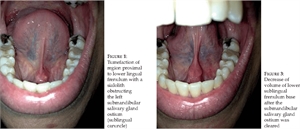

When there is a calculi present in the salivary duct, the obstruction of the salivary flow causes an inflammatory response. This condition is called sialolithiasis. When such an obstruction occurs in the submandibular or the sublingual region, it causes a swelling in the region of sublingual caruncle. The submandibular duct is the most affected duct in cases of sialolithiasis because of its tortuous course. Treatment of this includes extraction of the calculi causing the obstruction.